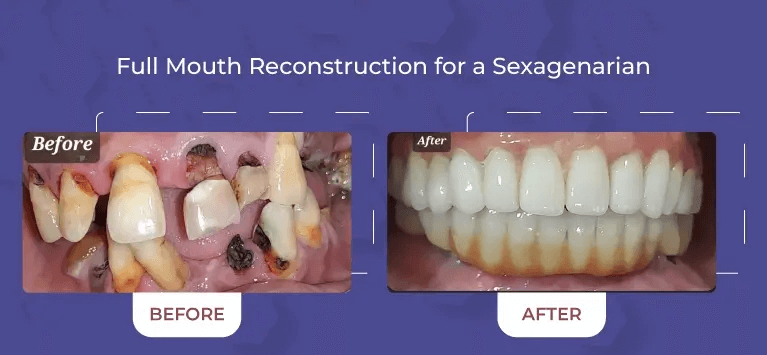

Comprehensive Services

From routine cleanings and preventive care to advanced cosmetic and restorative dentistry, we offer a full range of dental services to keep your smile healthy and vibrant.